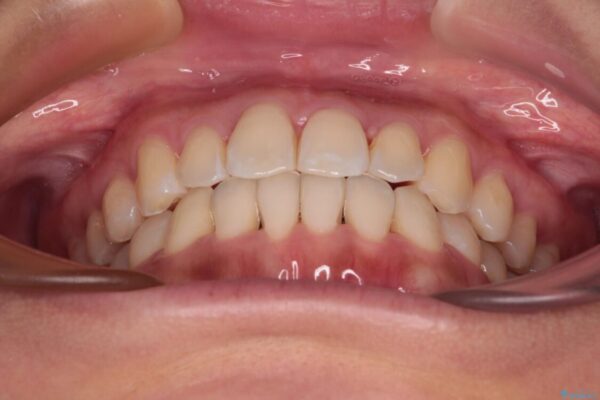

治療後について

装着時間を守ってくださったので、予定通りの期間で終えることができました。インビザライン特有の、奥歯の咬み合わせの問題もなく、しっかりと歯列を改善することができました。

治療後

• 【モニター】前歯のデコボコをインビザラインで改善 治療後画像